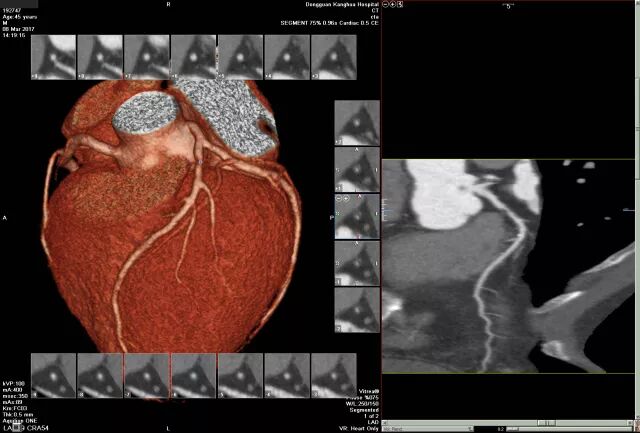

冠脉CTA:左前降支近端多发软硬斑块形成,管腔狭窄约80%。

DSA:前降支(LAD):近段可见85%狭窄,血流TIMI 3级。PCI:于狭窄段置入支架1枚。

小结:此病例中,患者具备典型心绞痛症状,冠脉CTA显示LAD近段管腔狭窄80%,可明确诊断冠心病。然而,CTA检查仅能提供冠脉狭窄情况判断,对显示心肌缺血程度、心肌活性判断等信息有所不足。TET可以增加心肌耗氧量,诱发心肌缺血,辅助临床对心肌缺血做出诊断;而心脏超声造影可显著提高心内膜边缘清晰度,使室壁运动异常的判断得到有效提升,同时,心肌造影可评价心肌灌注情况,对心肌活性预判提供有力支持。这两种技术的有机结合,使心肌缺血从心电图改变到心肌灌注异常,为临床诊治冠心病,治疗前方案选择,治疗后疗效判断及远期预后。